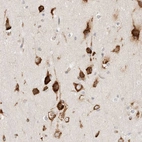

Immunohistochemical staining of human cerebral cortex shows strong cytoplasmic positivity in neurons.